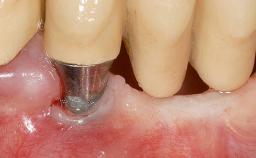

A 30-year-old woman was referred by her general dentist for evaluation of an esthetic complication related to previous implant treatment for congenitally missing maxillary lateral incisors. The patient’s chief complaint was the inadequate esthetic appearance of her smile. The case demonstrates the use of a combined approach to achieve optimal results. Two different flap designs - a tunnel technique and a coronally advanced flap - are employed based on the surgical objectives for the affected site.